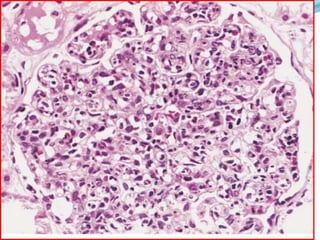

 Kidney-Lupus nephritis affects 50% of SLE patients.

 The principal mechanism of injury is immune

complex deposition in the glomeruli, tubular or

peritubular capillary basement membranes, or larger

blood vessels.

 Five patterns are recognized: minimal mesangial (class

I); mesangial proliferative (class II); focal proliferative

(class III); diffuse proliferative (class IV); and

membranous (class V).